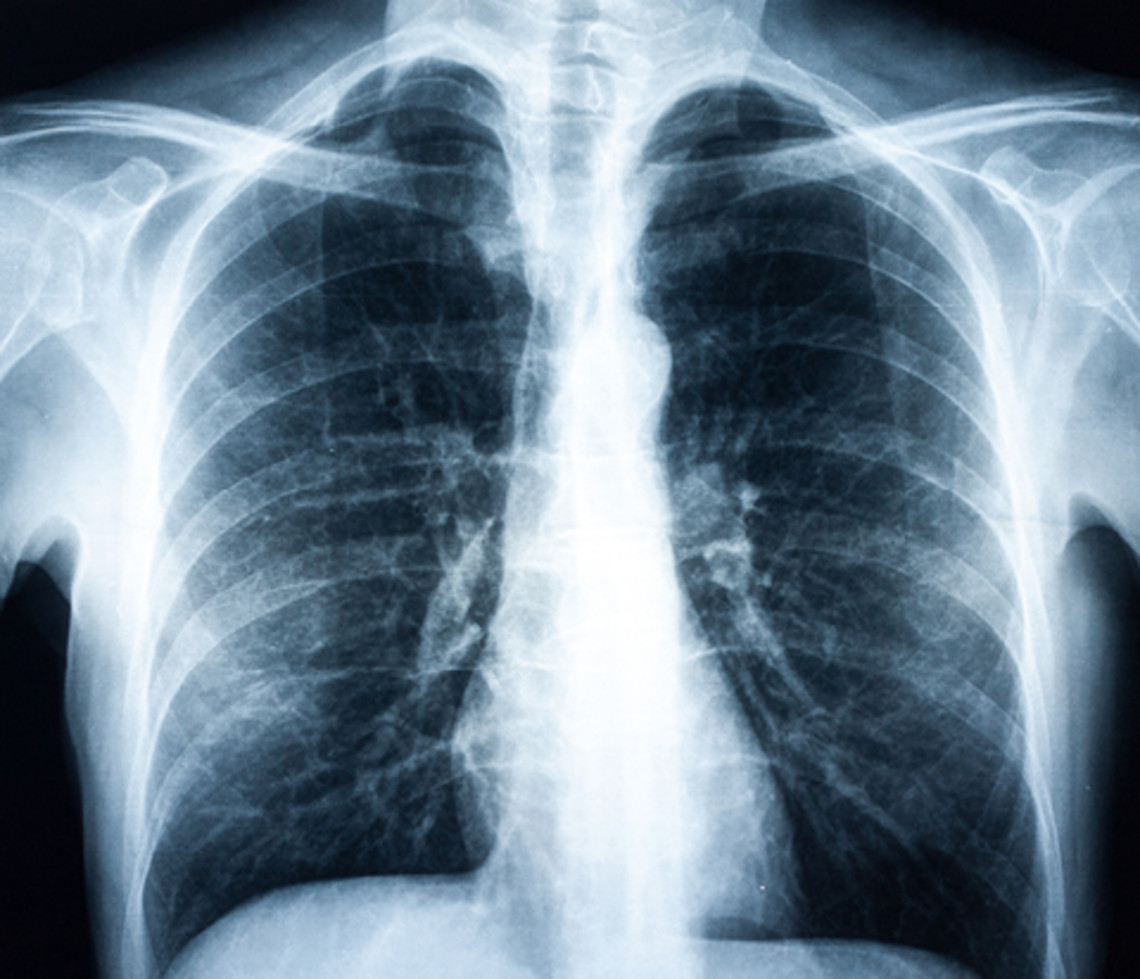

慢性阻塞性肺疾病的典型症状是呼吸短促、咳嗽和咳痰。胸部轻微紧绷也是慢性阻塞性肺疾病的个症状之一。60 岁以上男性吸烟者受慢性阻塞性肺疾病影响最大。不过,女性和更年轻的患者(约 40 岁以上)的比例在显著上升。遗憾的是,人们大大低估了这种疾病所带来的问题。慢性阻塞性肺疾病的典型症状往往被患者低估。

慢性阻塞性肺疾病有四个不同阶段。慢性阻塞性肺疾病病情越严重,患者就越快变得呼吸急促。在病情严重阶段,即使是简单的日常活动,如穿衣或脱衣,也会让患者上气不接下气。

慢性阻塞性肺疾病通常按照以下模式发展:慢性支气管炎经过多年发展成为慢性阻塞性支气管炎,例如,受吸烟习惯的持久影响。这导致支气管狭窄(阻塞),进而导致体力运动时呼吸短促。在晚期阶段,肺泡受损(肺气肿)。呼气更加困难,患者经常感到疲惫不堪。